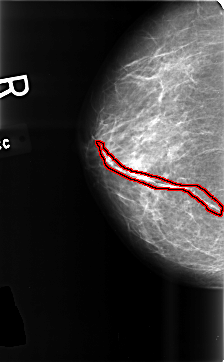

FILE: B_3435_1.RIGHT_CC.OVERLAY

TOTAL_ABNORMALITIES 1

ABNORMALITY 1

LESION_TYPE CALCIFICATION TYPE VASCULAR DISTRIBUTION N/A

ASSESSMENT 2

SUBTLETY 5

PATHOLOGY BENIGN_WITHOUT_CALLBACK

TOTAL_OUTLINES 1

BOUNDARY